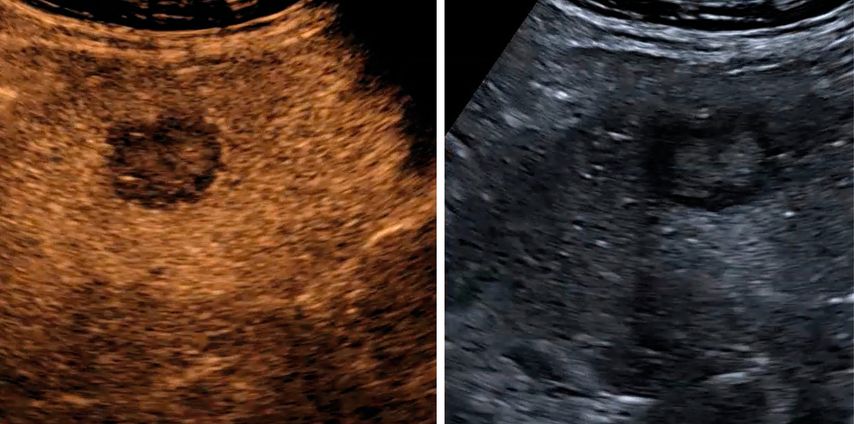

In der früharteriellen Phase zeigen benigne Läsionen wie Hämangiome typische Füllungsmuster ohne „wash-out“ in der Portal- oder Spätphase (Abb.1). Maligne Läsionen hingegen weisen meist ein rasches „wash-out“ auf und stellen sich in der Spätphase hypokontrastiert dar (Abb.2).3,4

Abb. 1: Typisches Kontrastmittelverhalten eines Hämangioms in der Spätphase mit Hyperenhancement gegenüber dem umgebenden Leberparenchym (rechts)

Abb. 2: Darstellung einer hochgradig Metastasen-suspekten Raumforderung bei Mamma-Neoplasie im linken Leberlappen im B-Bild-Modus (rechts) sowie in der Spätphase nach Gabe von 1,6 ml SonoVue® mit Darstellung eines deutlichen „Wash-out“-Phänomens in der Spätphase 4 Minuten nach Injektion des Kontrastmittels (links)